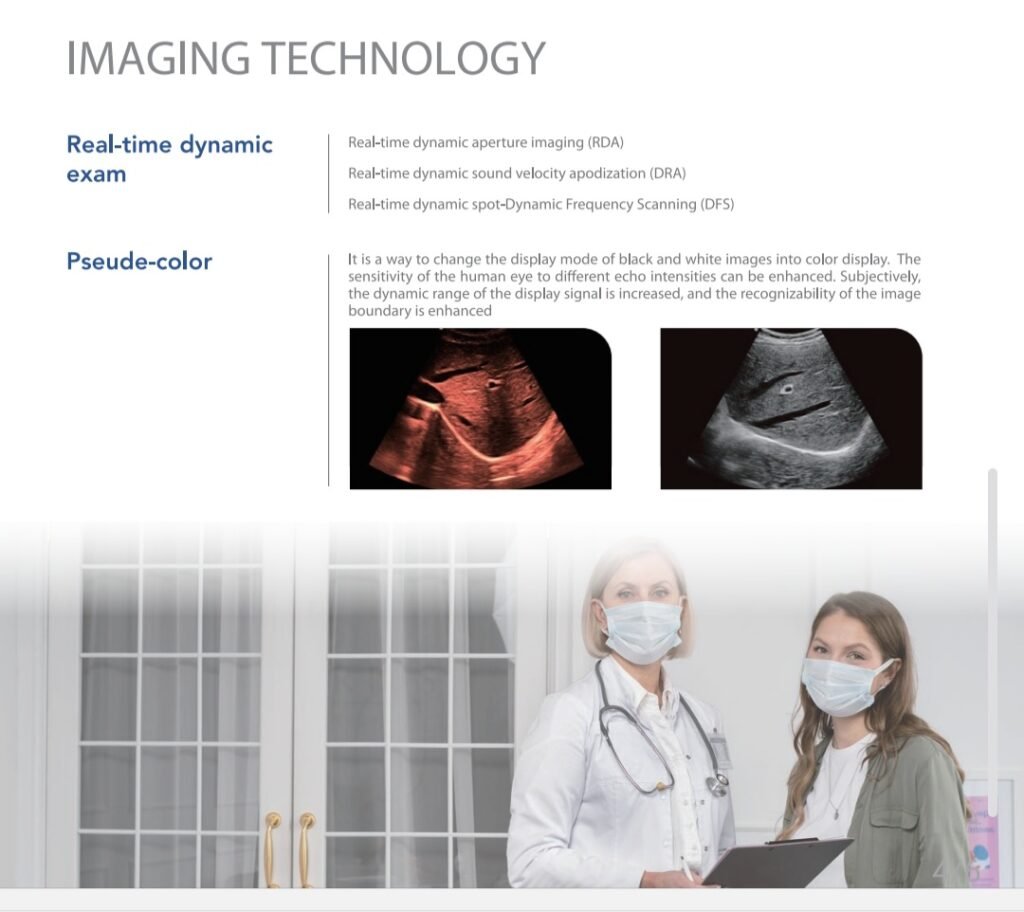

🖥️ Imaging Technologies for Clearer Diagnostics

The DAWEI DW-580 Laptop B/W Diagnostic Ultrasound Device utilizes real-time dynamic imaging and pseudo-color technology to enhance visualization during diagnosis.

Real-time Dynamic Imaging Features

-

RDA (Real-time Dynamic Aperture Imaging) – Enhances image resolution by dynamically adjusting the aperture.

-

DRA (Real-time Dynamic Sound Velocity Apodization) – Improves tissue differentiation and image quality.

-

DFS (Dynamic Frequency Scanning) – Enables smoother scanning and more detailed imaging for various body structures.

Pseudo-Color Imaging

Pseudo-color mode converts standard black-and-white ultrasound images into colorized visualizations, improving contrast sensitivity and image boundary recognition. This enhances diagnostic confidence, especially in soft tissue evaluations.